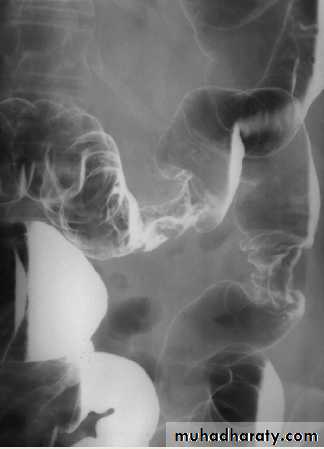

It is non-specific granulomatous inflammatory disease of unknown etiology, it nearly always affect the terminal ileum or other several parts of the small and large intestine, leaving normal intervening bowel, forming the skip lesions.The major radiological signs on barium examinations are :

1.strictures(string sign) are variable in length2.contraction of the cecum, this is seen with a diseased terminal ileum

3.dilatation of the bowel may be seen proximal to narrowed areas

4.ulcers :are quite deep. Fine ulceration + mucosal edema=cobblestone appearance

5.thickening,distortion and effacement of mucosal folds

6.separation of loops of bowel due to bowel wall thickening or an inflammatory mass

7.fistula to other loops of SB, colon, bladder or vagina

8.signs of malabsorption